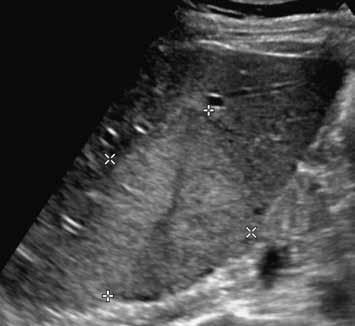

V UZ jsou patrná vícečetná izoechogenní ložiska (1, 2). U jiného pacienta (3) vidíme v játrech převážně hypoechogenní ložiska (žluté šipky) s naznačeným hyperechogenním periferním lemem (červené šipky). Po aplikaci kontrastní látky se ložiska patrná na obr. 1, 2 homogenně sytí a ani téměř po třech minutách nedochází k jejich vymývání (4–6).

Ultrazvukový obraz ukazuje většinou homogenní, někdy lobulované ložisko. V 60 % je hypoechogenní (obr. 1, 2), může však být izoechogenní nebo mírně hyperechogenní (obr. 3) vzhledem k normálnímu jaternímu parenchymu. Častěji se FNH vyskytuje v terénu steatotických jater. Ve 20 % případů nacházíme centrální jizvu.

V pravém laloku jater jsou na UZ lehce hypoechogenní ložiska s naznačeným výrazně hypoechogenním lemem (1, 2).

Na UZ je mezi kurzory patrné objemné nehomogenně hyperechogenní oválné ložisko (3).